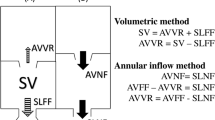

Levels of flow and shunt measurement. Systemic a and pulmonic b blood flows were measured at three different levels. Systemic flow a was measured at the aortic valve level [1], ascending aorta level [2] and as sum (3 = 3a + 3b) of the flow of the superior vena cava above the azygos vein (3a) and descending aorta (3b). When present, left persistent superior vena cava flow was added to the sum of SVC and descending aorta. Pulmonic flow b was measured at the pulmonary valve level [1], main pulmonary artery level [2] and as the sum of the right (3a) and left pulmonary artery flow (3b). Ventricular stroke volumes were calculated using magnitude images c. Additionally, shunt volumes were measured at the ASD level by septal tracking d

Management of ASD is mostly driven by the severity of cardiac shunting, defined by the pulmonary (Qp) and systemic (Qs) blood flow ratio [2, 5]. Three levels were used to obtain Qp and Qs flow: (1) valve, (2) main artery and (3) periphery (Fig. 2). The valve and vessels were tracked and “contoured” throughout the entire cardiac cycle [19]. Shunt fractions (Qp/Qs) were calculated for each level in all patients.

Alternatively, ventricular stroke volumes may be used for shunt fraction calculation, provided that no significant (≤ 20%) valve insufficiency is present. The study population was screened for valvular insufficiency, which was quantified if detected. In the subset of patients with no significant valvular insufficiency, the shunt fraction was calculated additionally using the right ventricular (RVSV) and left ventricular (LVSV) stroke volume ratio. For this, end-diastolic and end-systolic ventricular volumes were segmented from the 4D flow magnitude anatomic images [20]. Lastly, shunt volumes were measured at the atrial level by tracking the atrial septum (Fig. 2). Indirect shunt volume quantification was obtained by subtracting systemic from pulmonary blood flow (Qp–Qs).